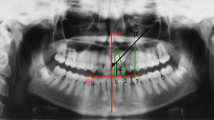

AMONG primates, sexual dimorphism in the size of permanent teeth is usually greatest for the canine tooth, that of the male exceeding that of the female by 3–7 per cent in Hylobates agilis and Homo sapiens and by nearly as much as 80 per cent in Papio anubis. Such dimorphism raises the theoretical question of whether the canine itself is exclusively involved, or whether the degree of sexual dimorphism spills over to adjacent teeth in the form of a “field”.